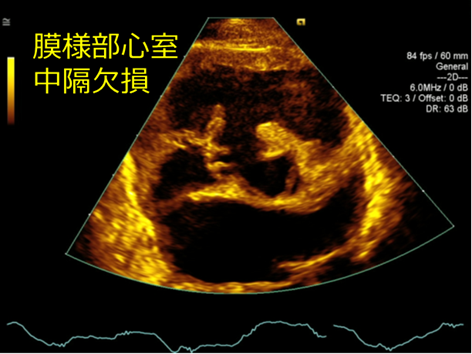

心室中隔欠損(VSD)とは

心室中隔に先天的に欠損がある状態のこと。

欠損孔を通して主に左室から右室への短絡があり、肺血流量が増え、心臓と肺への負担が増えます。